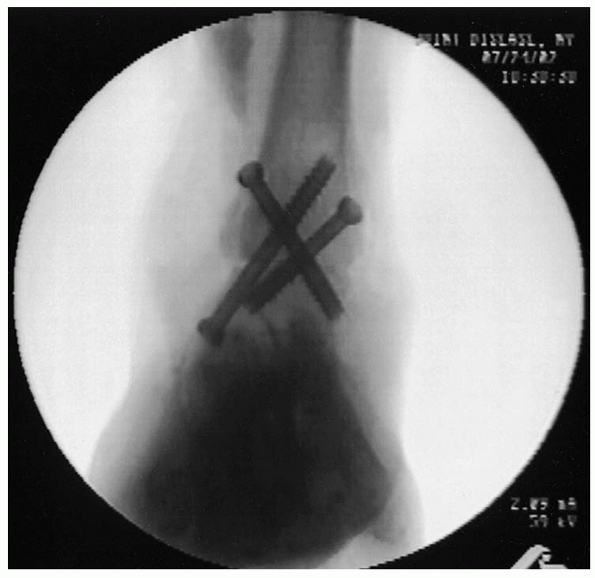

It is critical to check screw lengths radiographically and by direct

visualization if possible to avoid penetration of the subtalar joint,

which may lead to subtalar joint irritability. The medial screw may need to be countersunk to avoid prominent hardware in the subcutaneous medial tibia (Fig. 32-12). In the laboratory,

the cross-screw technique has been shown to be more biomechanically

sound than a plate-screw construct. The final construct is confirmed on

anteroposterior and lateral radiographs (Figs. 32-13 and 32-14).

FIGURE 32-13. Final anteroposterior view.

FIGURE 32-14. Final lateral view.